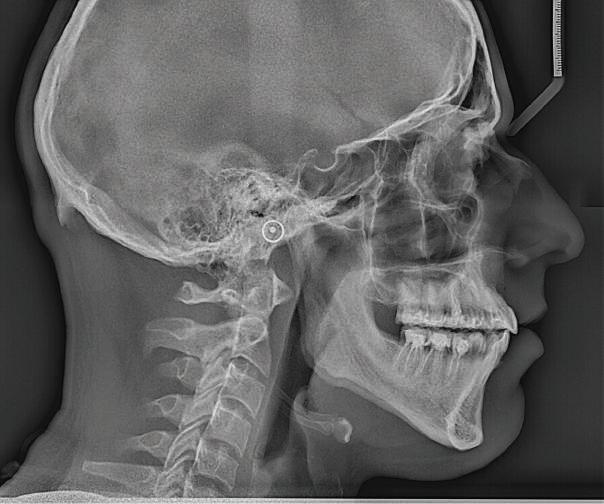

Пациент: 30 г., мъж Първо посещение: 02.08.2018 г. Основни оплаквания: Лицева болка, главо болие и болка в дясната темпоромандибу ларна става, естетични съображения РАБОТЕН ПРОТОКОЛ:

Пациентът постъпи в моята клини ка с наличие на темпоромандибуларен дисфункционален болков синдром, едно странно изместен диск с редукция в дяс ната става, клас II, подклас 2, тесни гор на и долна челюст със струпване, дъл бок овърбайт

орални снимки и снимки на позата, пал пация на мускулите, брукс-чекър, оклу зограми, кондилография, рентгеногра фии, СВСТ и ядрено-магнитен резонанс на темпоромандибуларните стави). Преди началото на ортодонтското лечение всички стари възстановява ния бяха свалени и бяха заменени с дъл госрочни временни от хибридна керами ка. На девитализираните зъби бе прове дено ендодонтско релечение. Индивиду ализиран оклузален сплинт бе направен с цел да се постигне контролирано репо зициониране на долната челюст, като носенето му продължи три месеца до възстановяване на правилната позиция на ставния диск и затихване на орофаци алната болка и дискомфорт в ставата. Брекетите в горната челюст бяха за лепени, за да започне подреждането и нивелирането на зъбите, докато паци ентът все още носеше сплинта. След края на терапията със сплинта бе на правена кондилография, за да се потвър ди триизмерната позиция на долната челюст. След залепване на брекетите в долна

и гингивална усмивка. Започнахме лечението с пълна диагно стика (анамнеза, интраорални, екстра